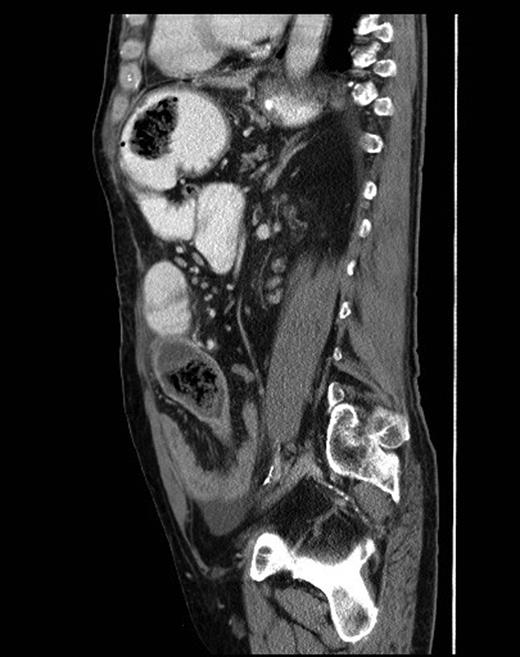

Sagittal CT scan view showing foreign bodies in the stomach and the ileum with transition point in the small bowel.